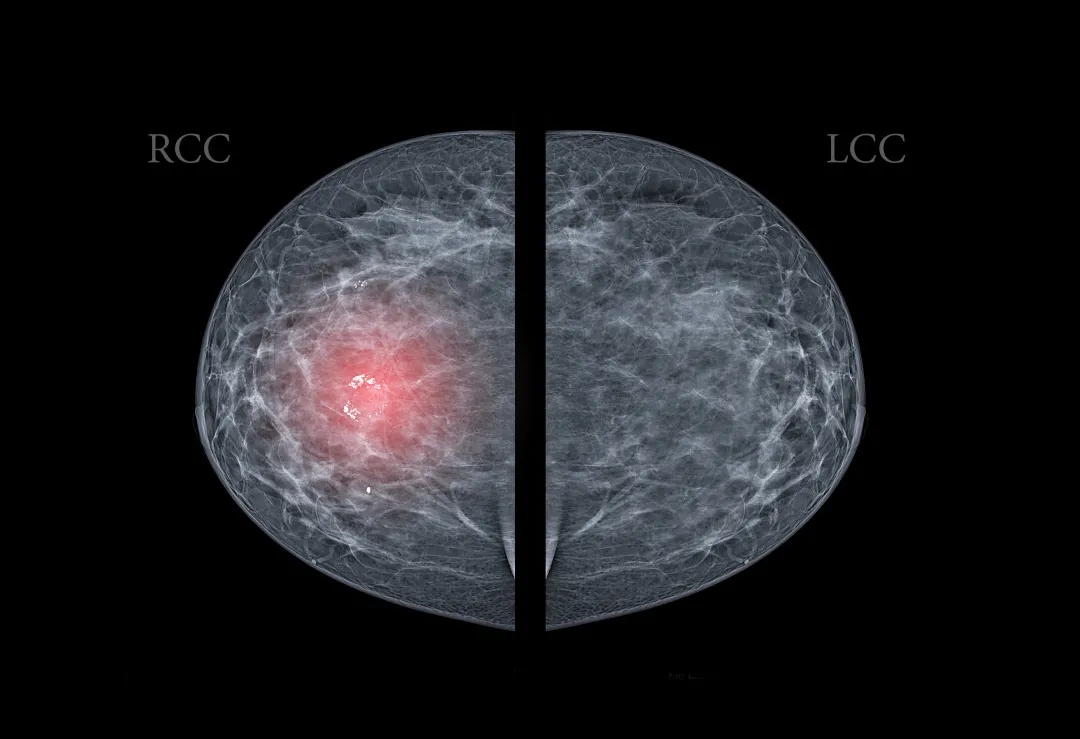

先要明確一點(diǎn),在我們體檢報(bào)告單上的“乳腺結(jié)節(jié)”并不是疾病名稱,而是一種影像觀察到的癥狀描述,當(dāng)B超、X線、CT等影像檢查發(fā)現(xiàn)你的乳腺上有個(gè)小腫塊時(shí),在性質(zhì)明確前,都可以被叫做乳腺結(jié)節(jié)[1]。

圖片來源于網(wǎng)絡(luò)

這種小腫塊可能是增生所形成的組織改變,也可能是乳腺良性腫瘤,甚至乳腺癌都有可能。但無論是哪種情況,乳腺結(jié)節(jié)一旦出現(xiàn)大多數(shù)情況下不會自己消失。